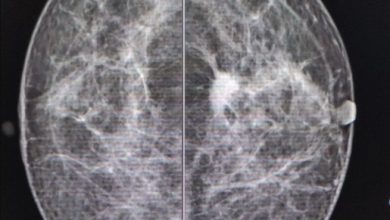

Recomienda la Secretaría de Salud acciones para detección oportuna del Cáncer de Mama

La Secretaría de Salud (SESA) del estado de Querétaro recomendó que se realicen acciones de prevención que permitan a las mujeres…